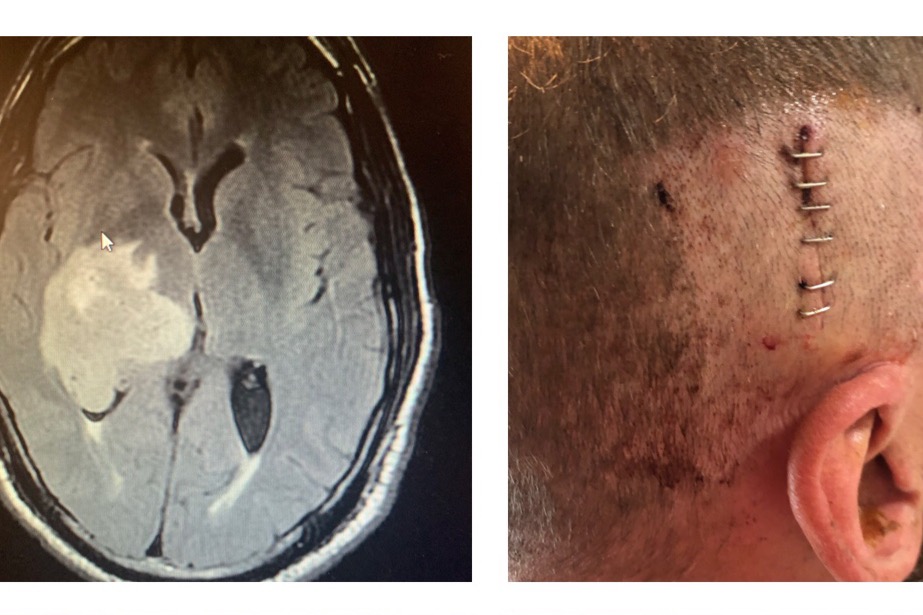

They did a CT scan to find a large mass and immediately took him to Mercy General in

Sacramento for further testing where they

discovered a large tumor.

Over the next couple of days they took images and did surgery for a biopsy on the tumor.